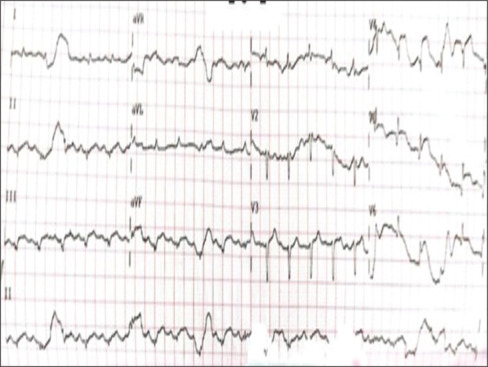

Takotsubo syndrome (TTS), also known as stress cardiomyopathy, is a life-threatening condition characterized by transient left ventricular dysfunction with nonischemic abnormalities. This syndrome in scenarios of anaphylactic shock is quite rare, with only a few cases reported. Early diagnosis and treatment are crucial. We presented a rare case of 58-year-old woman presented to our hospital due to an anaphylactic shock. The patient was stable and in the de-escalation dose of adrenaline (0.05 µg/kg/h). Twenty-two hours from exposure, the patient experienced pulmonary edema that required intubation, both adrenaline and dobutamine to maintain blood pressure. Echocardiography revealed a reduced ejection fraction of 35%. Subsequent coronary angiography showed no signs of coronary obstruction and left ventriculography provided typical apical ballooning and hyperkinesia in the basal region, highly suggesting TTS. The patient was successfully treated with inotrope and vasopressor and was discharged in stable condition after 7 days and improved normal heart function after 4 weeks. This case demonstrates the delayed onset of adrenaline-induced takotsubo complicated with pulmonary edema in a patient with anaphylactic shock due to antibiotics despite a de-escalation dose of adrenaline. Regardless of the duration of the event or the optimal epinephrine dosage in patients with anaphylactic shock, physicians should be aware of the risk of TTS.

Takotsubo综合征(TTS),也被称为应激性心肌病,是一种危及生命的疾病,其特征是短暂性左心室功能障碍伴非缺血性异常。在过敏性休克的情况下,这种综合征是相当罕见的,只有少数病例报道。早期诊断和治疗至关重要。我们提出一个罕见的病例58岁的妇女提出了我们的医院由于过敏性休克。患者病情稳定,肾上腺素降剂量(0.05µg/kg/h)。暴露22小时后,患者出现肺水肿,需要插管,肾上腺素和多巴酚丁胺来维持血压。超声心动图显示射血分数降低35%。随后的冠状动脉造影未见冠状动脉阻塞迹象,左心室造影显示典型的根尖球囊和基底区运动亢进,高度提示TTS。患者经肌力和血管加压药治疗成功,7天后出院,病情稳定,4周后心功能恢复正常。本病例显示了延迟发作的肾上腺素诱导的takotsubo并发肺水肿患者,尽管肾上腺素剂量降低,但抗生素引起的过敏性休克。无论过敏性休克患者的事件持续时间或最佳肾上腺素剂量如何,医生都应该意识到TTS的风险。